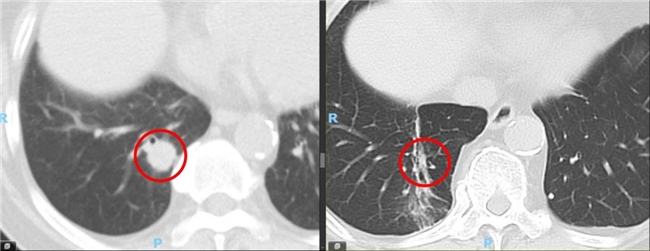

另一位80岁的王女士(化名),病情更为复杂。她不仅患有右肺早期腺癌,同时检测出EGFR L858R基因突变。面对高龄个体手术风险与肿瘤生物学特性,胡旭东主任团队制定了“SBRT局部根治联合靶向药物全身治疗”的个体化策略。

SBRT治疗顺利实施,后续复查显示肿瘤显著缩小。结合靶向药物治疗,患者病情得到全面控制。截至2026年3月的最新随访,患者状态稳定,治疗过程中未出现严重不良反应。